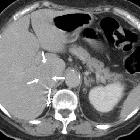

Isolated

intracaval recurrence of resected renal carcinoma. Follow-up contrast-enhanced CT after sunitinib therapy showed dramatic size decrease of tumor thrombosis (a, b) at six months (arrows) and only a small filling defect (c, d) at three years (arrows).

intracaval recurrence of resected renal carcinoma. Follow-up contrast-enhanced CT after sunitinib therapy showed dramatic size decrease of tumor thrombosis (a,b ) at six months (arrows) and only a small filling defect (c, d) at three years (arrows).